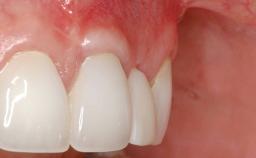

Variations in soft-tissue volume, evidenced either by an overabundance (Evian and coworkers 1993; Levine and McGuire1997; Dolt and Robbins 1997) or by a deficiency of soft or hard tissue can complicate implant-supported rehabilitations in the esthetic zone (Lorenzana 2008; Lorenzana and coworkers 2009). The present case illustrates the replacement of a failing upper left lateral incisor complicated by generalized severe gingival recession in the esthetic zone.